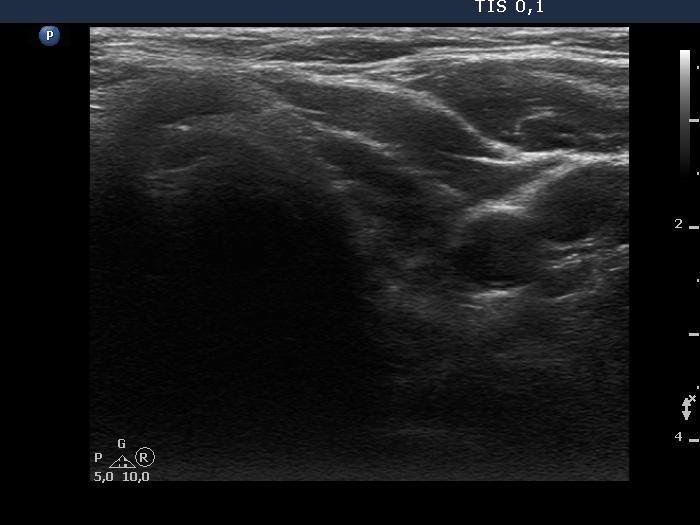

Two years after the initial examination (ultrasonographic picture 6)

Left lobe, trasnverse scan. This lobe remained unchanged.